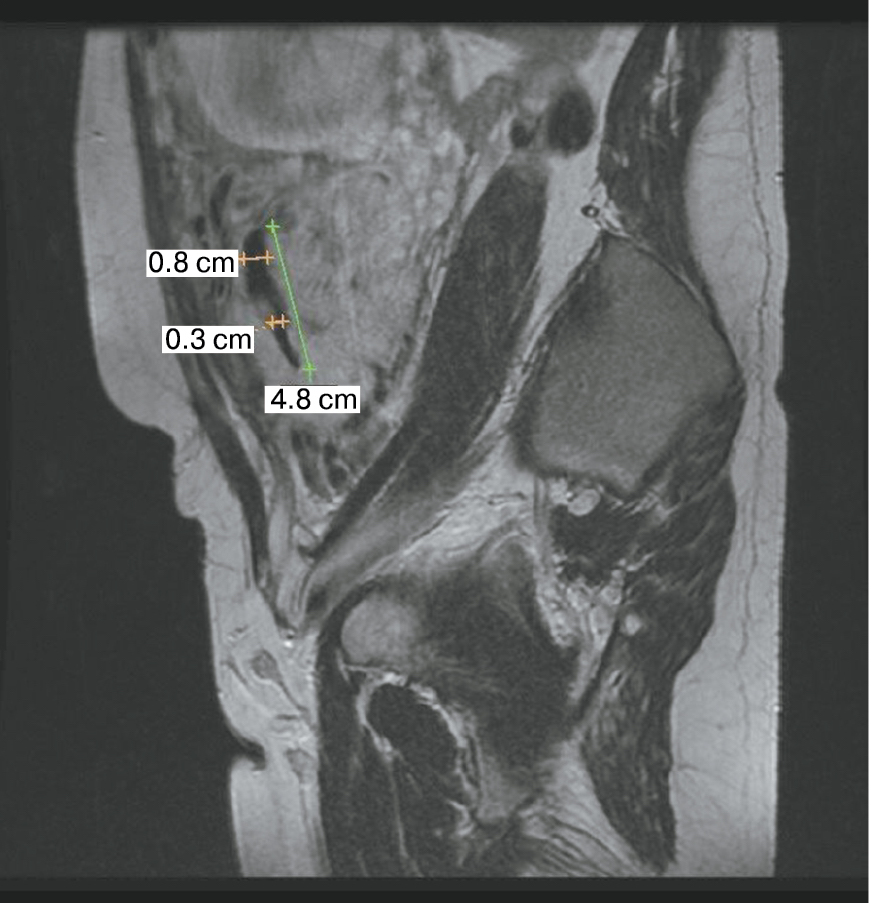

Является ли симптом «обнаженного сосуда» патогномоничным для параметральной инвазии или нет, еще предстоит выяснить; однако в ходе исследования установлена его связь с частотой гистерэктомий в группах с наличием симптома «обнаженного сосуда», что, вероятно, обусловлено мощной сосудистой сетью коллатералей и неоангиогенезом. Во всех случаях обнаружения данного признака впоследствии была выполнена вынужденная гистерэктомия (рис. 3–6, пациентка Н., 37 лет).

Рис. 5. Корональная проекция МРТ. 1 – интрамуральная гиперваскуляризация; 2- измененный контур мочевого пузыря